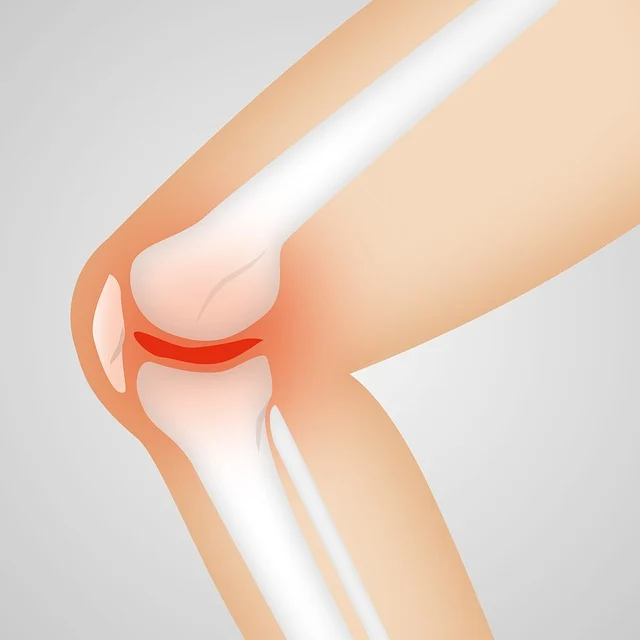

관절염은 관절의 염증으로 인해 통증과 부종을 유발하는 질환입니다. 이 질환은 여러 가지 형태가 있으며, 대표적으로 osteoarthritis(퇴행성 관절염)와 rheumatoid arthritis(류마티스 관절염)이 있습니다. 두 종류 모두 관절에 영향을 미치지만, 그 발생 원인과 증상은 다르게 나타납니다.

퇴행성 관절염은 일반적으로 나이가 들면서 발생합니다. 이 형태의 관절염은 관절의 연골이 마모되면서 점차 악화되는 현상인데요, 이는 오랜 시간 동안의 반복적인 스트레스나 과사용으로 인해 발생할 수 있습니다. 퇴행성 관절염은 무릎, 엉덩이, 손가락에 주로 발생하며, 증상으로는 통증, 뻣뻣함, 움직일 때 소리가 나는 등의 특징이 있습니다.